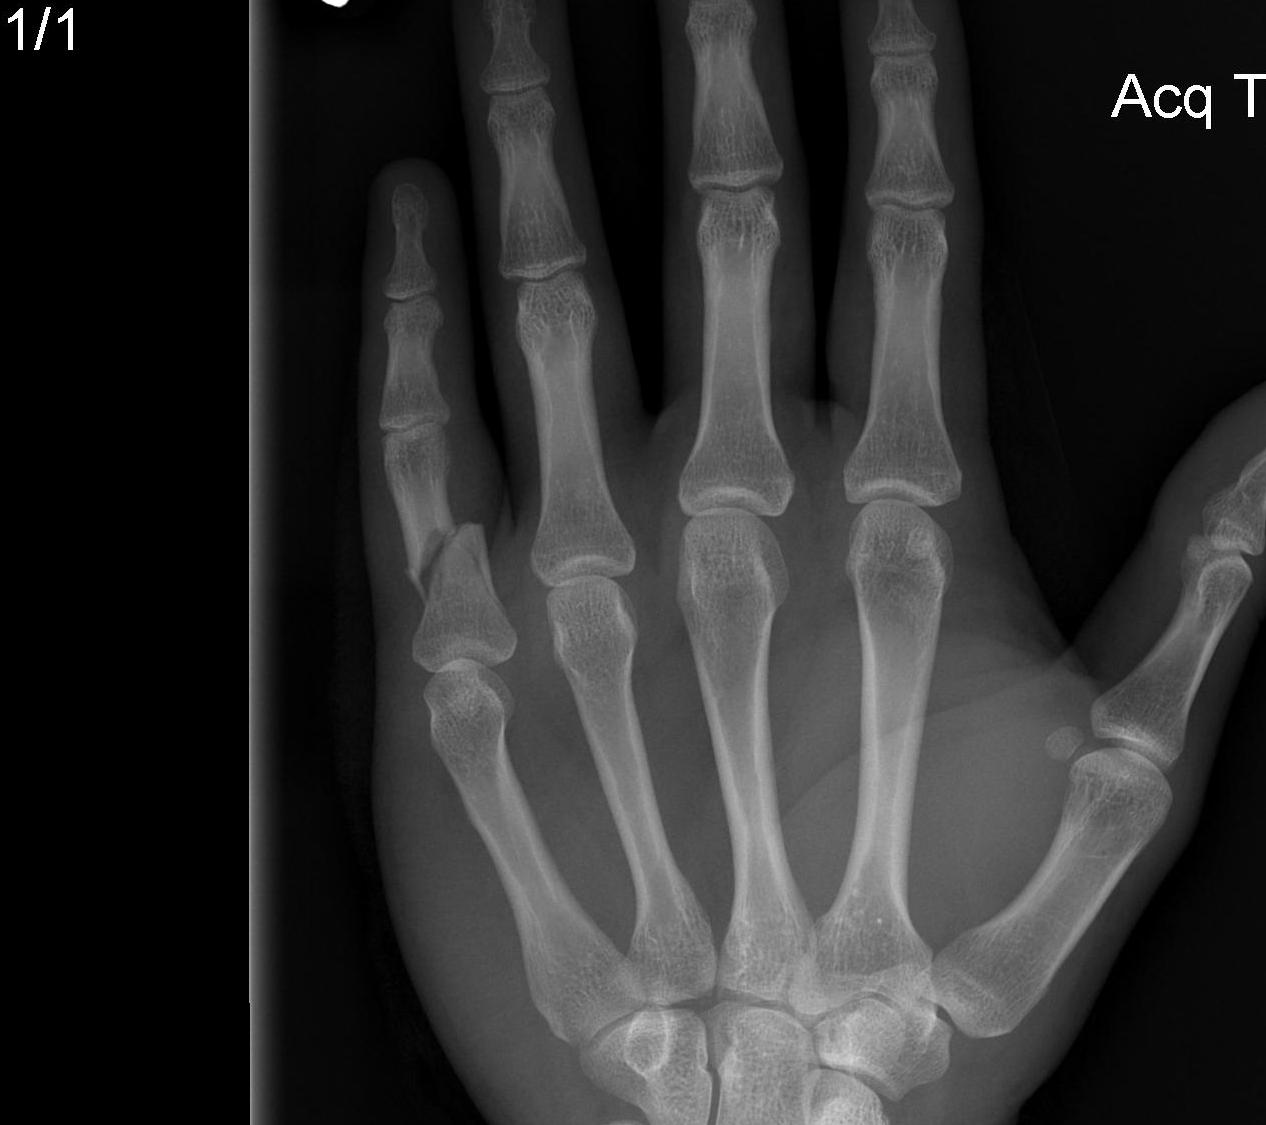

X-rays

3 planes centred on MCPJ middle finger

- AP

- lateral

- oblique

Care to look for subtle evidence joint subluxation